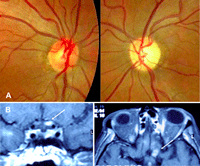

Figura 4. Neuropatía óptica infiltrativa. Paciente fumador de 65 años que consultó por pérdida visual subaguda en el ojo izquierdo, presentaba un defecto pupilar aferente y visión de no percepción luminosa. Figura 4A. Fondo de ojo: Se observó una discreta palidez temporal del disco óptico izquierdo sin elevación ni borramiento de los márgene. Se practicó un estudio de imagen cerebral por sospecha de afectación retrobulbar. Figura 4B. Resonancia magnética cerebral coronal T1 con contraste. Se detectó una lesión que comprimía e infiltraba la porción intracraneal del nervio óptico izquierdo. La captación de contraste en otros nervios craneales sugería un proceso meníngeo infiltrativo y múltiple. Figura 4C. Tomografía de emisión de positrones-TC torácico. Reveló la presencia de un nódulo pulmonar hipercaptante compatible con neoplasia pulmonar responsable de una carcinomatosis meníngea.

Figura 9. Neuropatía óptica por irradiación. Una mujer de 45 años con antecedentes de carcinoma de nasofaringe, irradiado y tratado con quimioterapia consultó por pérdida visual subaguda en el ojo izquierdo sugestiva de neuropatía óptica. Figura 9A. Fondo de ojo: Es normal en el ojo derecho y hay palidez papilar en el izquierdo. Figura 9B. Resonancia magnética craneal T1 con gadolinio. La flecha indica el realce de contraste en la porción intracraneal del nervio óptico izquierdo en los cortes coronales (arriba) y axiales (abajo) No se apreciaron anomalías en las secuencias T1 y T2. Estos hallazgos, confirman que la causa del deterioro visual es la radioterapia y se descarta la compresión o infiltración del nervio.